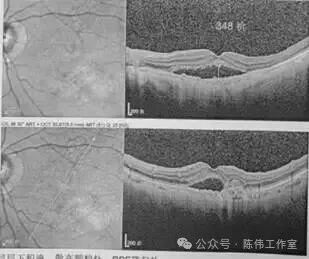

陈伟院长根据老人详尽的眼底检查结果,为他的右眼量身定制了第一步“光明攻略”——抗VEGF治疗。这是一种通过眼内注射药物,“狙击”导致黄斑水肿的异常血管因子的方法。一个疗程结束,复查结果较为理想:黄斑水肿由原来的348降至114。